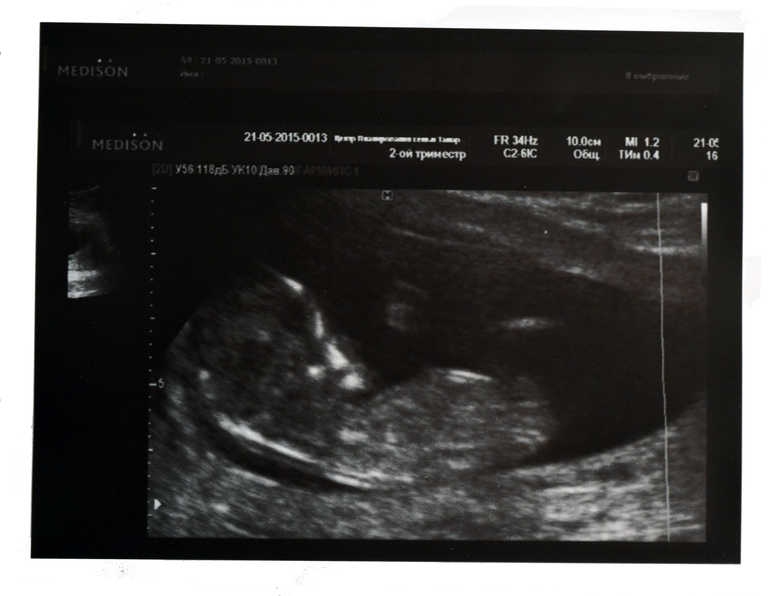

Врач стала комментировать все свои действия водя датчиком по животу. У нас с мужем была своя большая плазма и мы все прекрасно видели. Так вот. меряет она меряет ручки ножки....рассказывает., а у меня от счастья наворачиваются слезы. Но когда кроха нам с экрана помахал ручонкой - муж аж воскликнул с восторгом, вот тогда я уже слез сдержать и не смогла.

В общем по узи у нас порядок, растем по срокам. Муж (ну и я само собой) остался доволен. Весь вечер мы потом вспоминали эту ручку и махали друг другу.